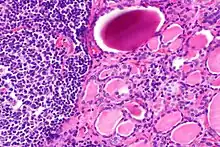

| The thyroid of someone with Hashimoto's thyroiditis as seen with a microscope at low magnification | |

Gross pathology of a thyroid with autoimmune thyroiditis may show an symmetrically enlarged thyroid.[22] It is often paler in color, in comparison to normal thyroid tissue which is reddish-brown.[22] Microscopic examination will show infiltration of lymphocytes and plasma cells. The lymphocytes are predominately T-lymphocytes with a representation of both CD4 positive and CD8 positive cells.[22] The plasma cells are polyclonal, with present germinal centers resembling the structure of a lymph node.[22] Fibrous tissue may be found throughout the affected thyroid as well.[22] Generally, pathological findings of the thyroid are related to the amount of existing thyroid function - the more infiltration and fibrosis, the less likely a patient will have normal thyroid function.[22] In late stages of the disease, the thyroid may be atrophic.[12]

Histologically, the hypersensitivity is seen as diffuse parenchymal infiltration by lymphocytes, particularly plasma B-cells, which can often be seen as secondary lymphoid follicles (germinal centers, not to be confused with the normally present colloid-filled follicles that constitute the thyroid). Atrophy of the colloid bodies is lined by Hürthle cells, cells with intensely eosinophilic, granular cytoplasm, a metaplasia from the normal cuboidal cells that constitute the lining of the thyroid follicles. Severe thyroid atrophy presents often with denser fibrotic bands of collagen that remains within the confines of the thyroid capsule.[52]

It is also characterized by invasion of the thyroid tissue by leukocytes, mainly T-lymphocytes. A rare but serious complication is thyroid lymphoma, generally the B-cell type, non-Hodgkin lymphoma.[53]